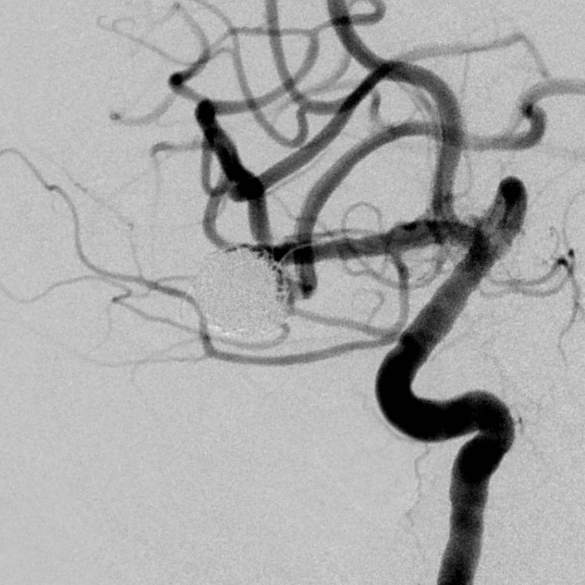

粗大分支从破裂瘤体上发出来,急性期能单纯致密栓塞吗?

病史:中年女性,新冠感染,颅内动脉瘤破裂,Hunt-Hess 4级

最终,动脉瘤瘤体致密栓塞,各个分支保留良好